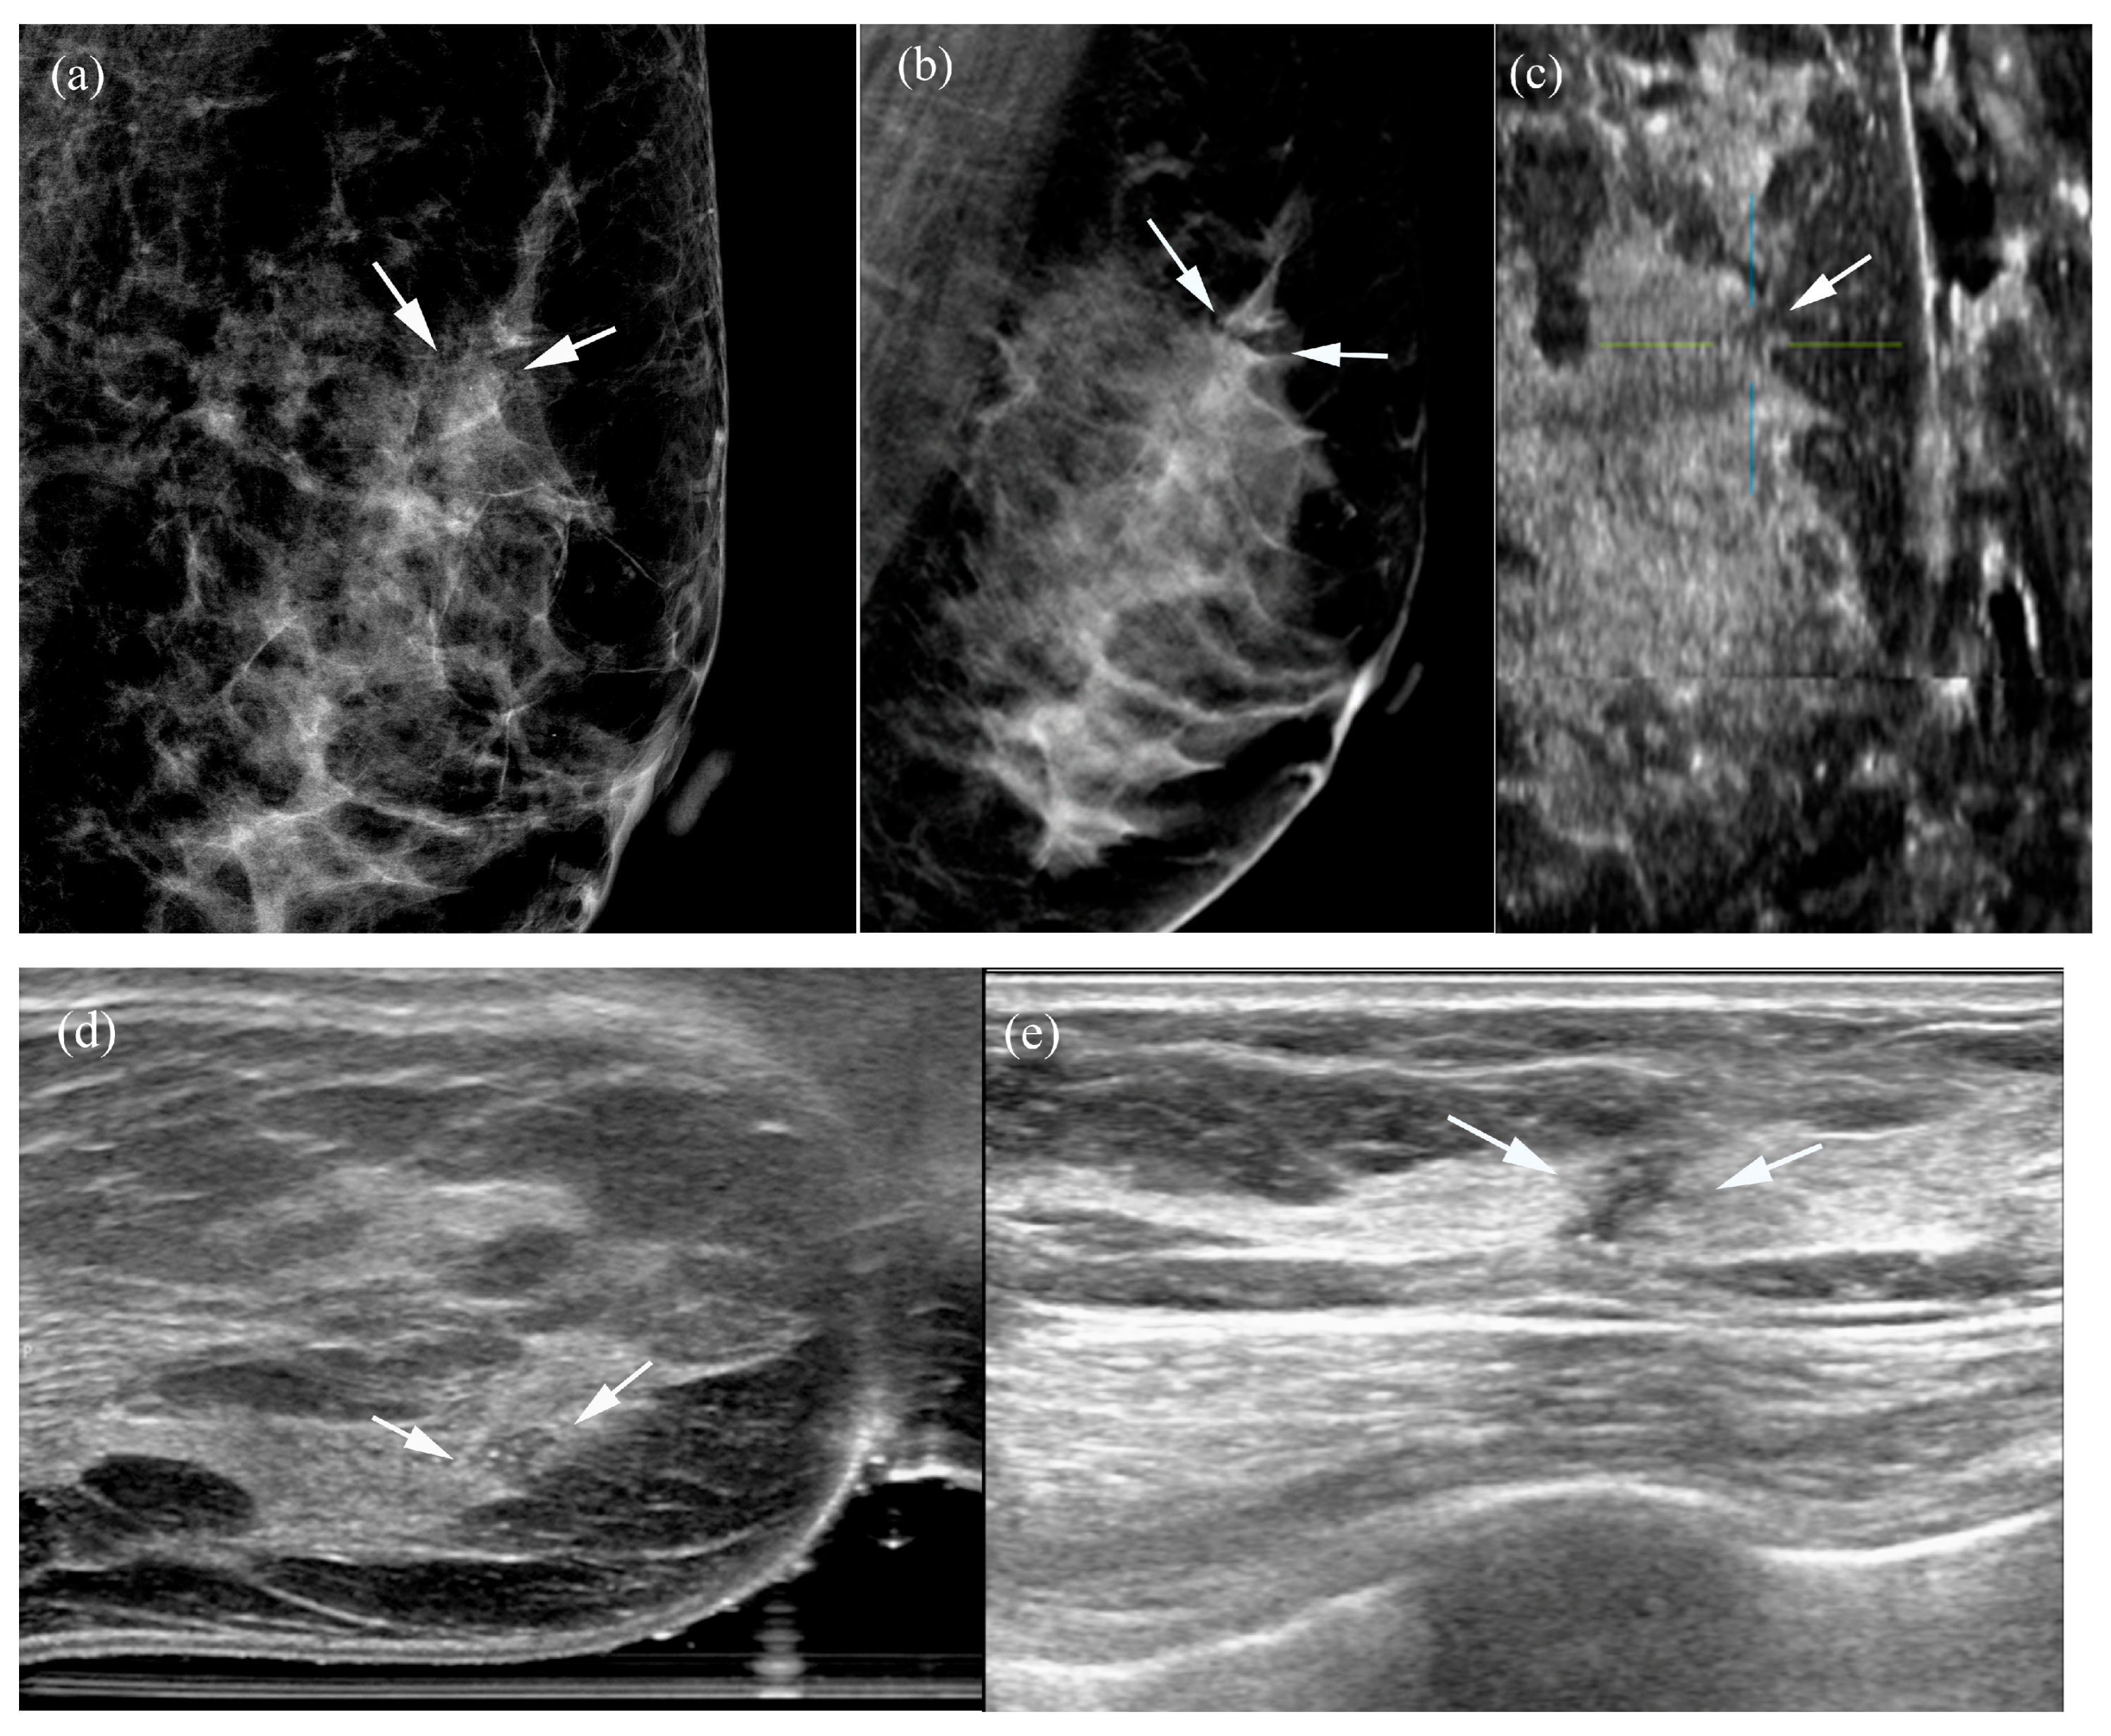

Table 5 summarizes the factors influencing lesion visibility on DBT and MammouS-N images. Lesions that were better visualized on MammouS-N included masses obscured on DBT and non-calcified lesions (p ≤ 0.005) (Figure 4 and Figure 5). Reviewer 2’s assessment showed that larger lesions tended to be better visualized using DBT. No significant associations were observed between lesion visibility and factors such as patient age, mammographic density, lesion size on MammouS-N, echotexture, or lesion type (Figure 6).

Lesion characteristics strongly influenced the visibility differences between the two modalities. Non-calcified lesions received high visibility scores on both DBT and MammouS-N, according to both reviewers. However, DBT demonstrated superior performance in detecting calcified lesions, accounting for 44% of the cases in this study. This result was expected, as tomosynthesis is particularly effective for detecting calcifications owing to its high-contrast appearance, whereas ultrasound generally has limited sensitivity for microcalcifications unless they are associated with a mass or non-mass lesion [14,15]. On MammouS-N, 93% of the lesions were classified as masses, and only 7% were classified as non-mass lesions. This distribution suggests that MammouS-N may be particularly valuable for enhancing the detection and characterization of mass lesions, particularly smaller lesions without associated calcifications, which may be more challenging to identify using DBT.

Figure 6. A 56-year-old woman with ductal carcinoma in situ: (a,b) Two-dimensional and three-dimensional left mediolateral oblique mammograms demonstrate grouped pleomorphic microcalcifications and associated architectural distortion (arrows). (ce) MammouS-N sagittal (c) and transverse (d) images of the left mediolateral oblique view reveal an irregular, angular hypoechoic mass containing internal echogenic foci (crosshairs, arrows), representing microcalcifications. These findings align with the features observed on the corresponding handheld ultrasound image (e).